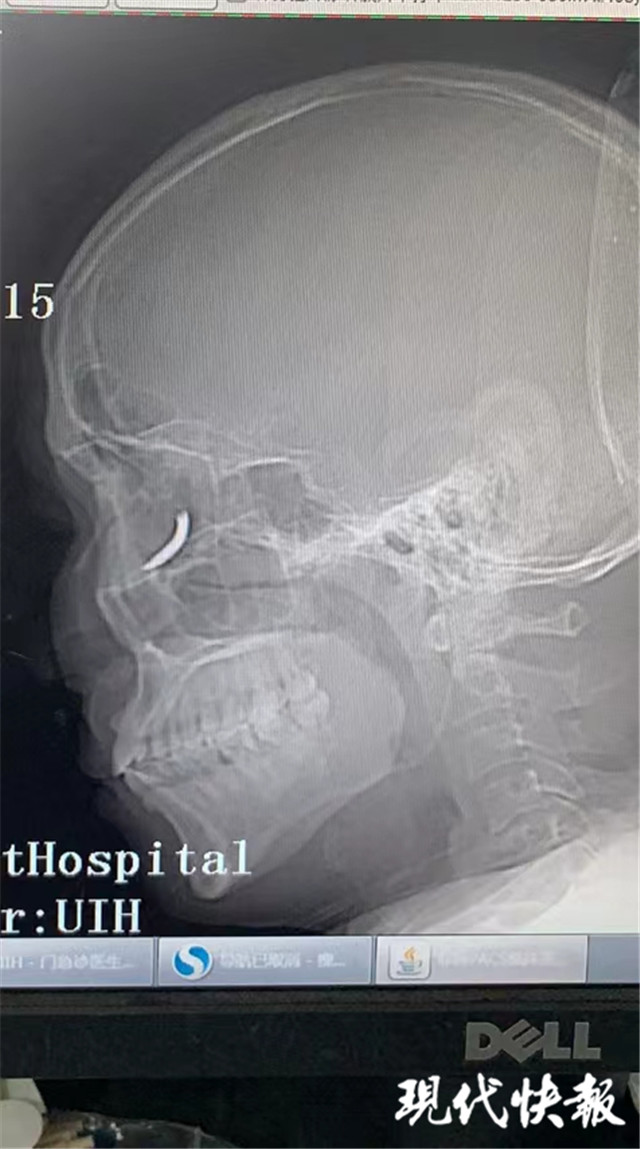

(通訊員 孫忠河 記者 梅書華)鐵釘扎入眼眶,卻不疼不癢,這是怎么回事?三天前,王師傅在溧水的建筑工地干活時(shí),突然感覺有異物進(jìn)入眼內(nèi),但沒當(dāng)回事,后來出現(xiàn)頭暈才就診,沒想到是鐵釘扎入了眼眶。南京市第一醫(yī)院醫(yī)生通過半小時(shí)手術(shù),順利將一根長約一公分的鐵釘取出。

“當(dāng)時(shí)在敲鐵釘,感覺什么東西進(jìn)眼睛里了,但沒影響視力,還以為是水泥灰之類的。”三天前,王師傅眼中進(jìn)入異物,感覺頭暈不適后,去當(dāng)?shù)蒯t(yī)院就診,拍了X光片后,竟然發(fā)現(xiàn)自己眼眶內(nèi)有一個(gè)鐵釘樣的異物。

隨即,王師傅趕到南京市第一醫(yī)院眼科就診,眼科門診曹雪倩醫(yī)生接診后,立即完善CT等相關(guān)檢查。剛準(zhǔn)備休息的眼科醫(yī)生范偉杰,立即與副主任醫(yī)師趙貴陽聯(lián)合研究這個(gè)特殊的病例。專家們發(fā)現(xiàn)這枚鐵釘不偏不倚正好扎進(jìn)病人的眼眶里,但是眼眶內(nèi)解剖結(jié)構(gòu)復(fù)雜,要在盡可能保護(hù)正常組織結(jié)構(gòu)的情況下完成探查并取除鐵釘,手術(shù)難度較大。

范偉杰與趙貴陽反復(fù)討論后,制定了詳細(xì)周密的手術(shù)方案,最終以局麻下、眼袋美容切口進(jìn)入,順利取出了一根長約一公分的鐵釘。整臺(tái)手術(shù)耗時(shí)半小時(shí),手術(shù)過程中沒有損傷到眼球壁和視神經(jīng),但醫(yī)生發(fā)現(xiàn)因?yàn)殍F釘?shù)那秩?,視網(wǎng)膜周邊有出血,所以做了視網(wǎng)膜光凝。術(shù)后視力1.0,面部看不出瘢痕。王師傅的眼球終于安全保住了。